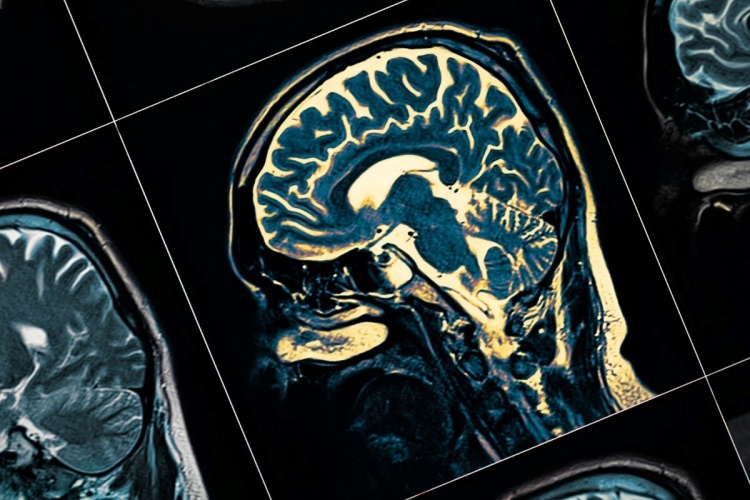

Avustralya'daki bir yaşındaki Bella, aniden gelişen sağlık sorunları sonucu ailesini ve doktorları şoke etti. Topallama şikayetiyle hastaneye götürülen minik kız, yapılan testlerin ardından çocukluk çağı demansı teşhisiyle karşılaştı. Aile, bu beklenmedik durumla başa çıkmaya çalışırken, Bella'nın hayatı hızla değişti. Avustralya'da yaşayan Abbe Baker, bir yaşındaki kızı Bella'nın topallamaya başlamasıyla birlikte tıbbi bir kabusun içine girdi. anne, parktaki oyun sırasında fark ettiği bu durumu eşiyle paylaştıktan sonra, Bella’yı hastaneye götürdü. Röntgen sonuçları kırık veya burkulma belirtisi göstermedi, ancak Bella’nın durumu hızla kötüleşti.Bella'nın vücudunun sol tarafında güç kaybı ve ağrılı kas spazmları yaşanmaya başladı. Nörologlar, başlangıçta viral bir enfeksiyon düşündü, ancak yapılan testlerin negatif çıkması endişeleri artırdı. Bella, felç benzeri semptomların nedenini bulmaya çalışmak için hastanede MRI, kan testleri, lomber ponksiyon ve genetik ve metabolik testler yaptırdı. Bella'nın gücü azalmaya devam ederken yapılan testlerin hiçbiri pozitif çıkmadı. iki hafta içinde konuşma yeteneğini kaybeden bebeğin eski halinden eser kalmamıştı. Ailesi "Çok zeki bir kızdı, bir yaşındayken beş kelimelik cümleler kurabiliyordu" ifadelerini kullandı.Aile, Bella'nın Segawa Sendromu olabileceğini düşündü, ancak doktorlar bunun yerine çocukluk çağı bunaması ile ilişkili bir rahatsızlığa yakalandığını belirtti. Anne "Doktor kesinlikle nörolojik regresif bozukluğa sahip olduğunu söyledi, bu da temelde bunamanın başka bir terimidir" dedi.Daha dar bir ölçekte test yapılması gerektiğinden, Bella'nın hangi tür demansa sahip olduğunu belirlemek için bir dizi yoğun test daha yapıldı. Sonuçların Kasım ayında çıkacağı belirtilirken Aniden ortaya çıkan ciddi hastalık, bebeğin ve ailenin hayatını tamamen değiştirdi.Baker, "Evimizi satıp hastaneye daha yakın olmak taşınmayı düşüneceğiz çünkü her hastalandığında durumu çok çabuk kötüye gidiyor." dedi. Yüreği buruk anne, Yaşayan bir cehennemde olduklarını ve kızının sıkıntılarına alıştıklarını söyledi.Baker, "Çocuğumuzun acı çektiği gerçeğine duyarsızlaşmak zorunda kalmamız gerçekten korkunç." dedi. "Kan testleri beni onun için ağlatırdı ama şimdi ona karşı bağışıklık kazandım çünkü o 7/24 acı çekiyor. Durmaksızın." diye konuştu.